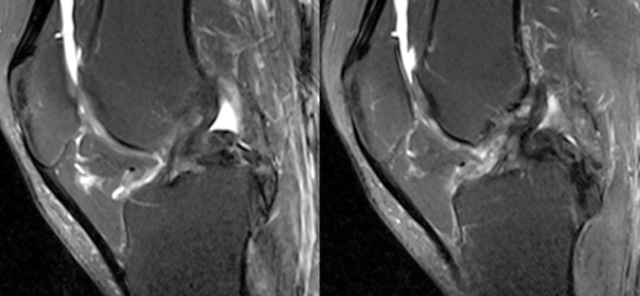

(七)ACL损伤直接征象

1)ACL本身的形态和信号异常:

2)不连续:

有韧带的低信号,但中断不连续。

一般见于新鲜损伤。

3)方向异常(ACL 下垂征):

有较完整的韧带低信号,但方向异常,呈下垂状。

一般见于股骨附着部的陈旧损伤,损伤的ACL下垂并粘附在PCL上。

4)消失:

髁间窝空虚,无韧带信号。

见于较久的损伤,损伤的ACL撕裂较重呈马尾状,无滑膜包裹,逐渐被关节内的酶腐蚀而消失。